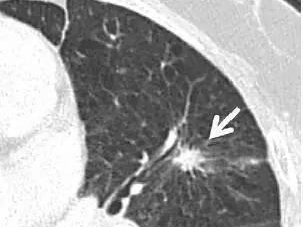

图3:周围型肺癌